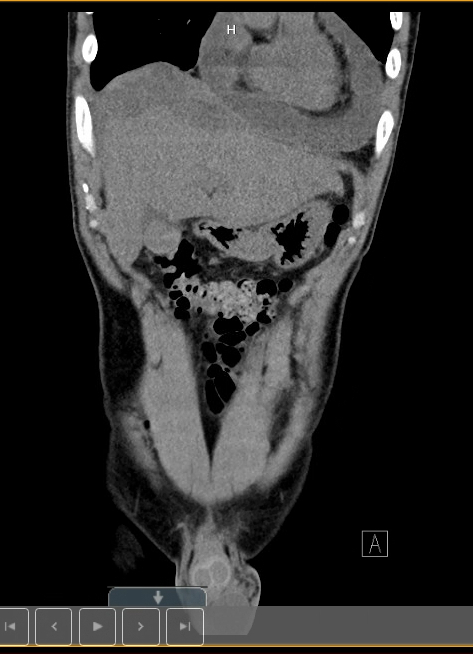

Our case is a 51-year-old male with a past medical history of multiple sclerosis who presented to the emergency department with vomiting, chest pain, and shortness of breath. The EKG on admission was concerning for ST elevation in the inferolateral leads, but it resolved without any intervention. He had normal troponins. 2-D echocardiogram showed moderate to large circumferential pericardial effusion with mobile echodensities along the RV without evidence of cardiac tamponade physiology. CT of the abdomen and pelvis also revealed low attenuation in the left hepatic lobe that was concerning for liver abscess with free fluid in the pelvis. Pericardiocentesis was done and yielded 500 ml of straw-colored fluid. An ultrasound-guided pigtail catheter was inserted for the liver abscess, which drained 70 ml of purulent fluid. Cultures from the pericardial fluid yielded Parvimonas mica. The patient was treated empirically with piperacillin-tazobactam and was later switched to ceftriaxone. However, a repeat echocardiogram done a few days later showed reaccumulation of purulent pericardial effusion, which required a pericardial window. The patient also developed bilateral pleural effusions after the pericardial window. Drainage of right pleural fluid yielded 950 ml of neutrophilic predominant fluid. Afterwards, he improved clinically and was discharged with a four-week course of IV ceftriaxone followed by PO Augmentin for another four weeks.